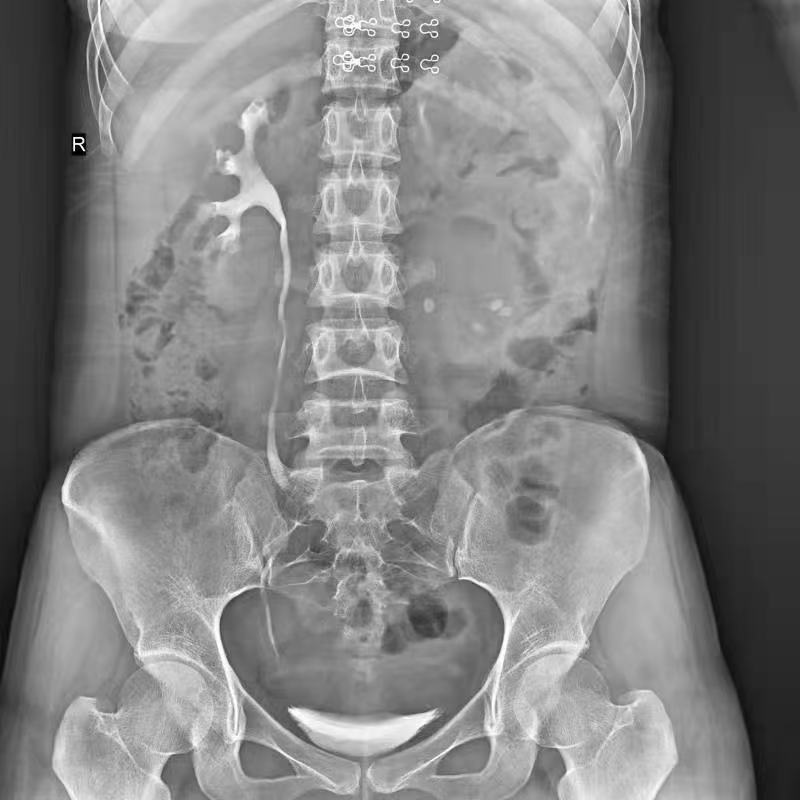

普利德醫(yī)療自主研發(fā)的新一代數(shù)字化X線透視攝影系統(tǒng),可應用于DR攝影、數(shù)字透視、數(shù)字造影以及可視化精準DR拍片等多種臨床X線檢查領域。

● 17*17英寸的超高清像素動態(tài)平板探測器,更大的視野范圍,無需移動即可觀察整個動態(tài)過程,避免拖尾、噪聲對圖像的影響;

● 高效動態(tài)平板技術,圖像不會有幾何畸變,提供高分辨率和精確的圖像,為醫(yī)生臨床診斷提供精準依據(jù);

● 最高幀速可達30幀/秒,動態(tài)采集清晰流暢,避免漏診、誤診情況的發(fā)生;

● 在可視過程或回放過程中,如發(fā)現(xiàn)疑似病灶,可進行毫秒級高清點片,隨時抓取單幀圖像,精準捕抓病灶。

點片裝置移動范圍大,無需患者移動就能完成全身各部位的檢查;

床面橫向移動,輕松實現(xiàn)機動人不動。